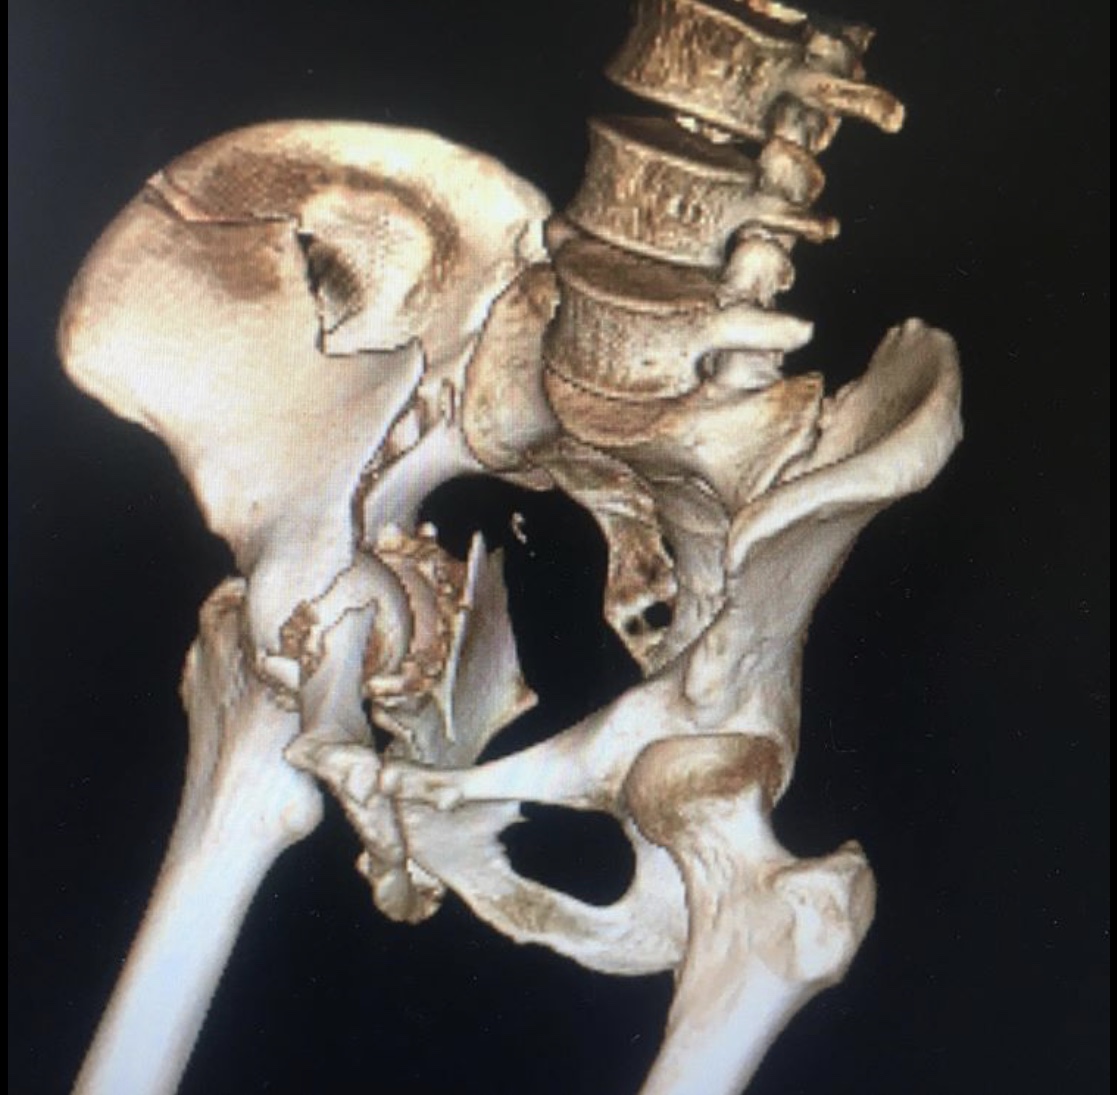

Ещё один случай тяжелой травмы вертлужной впадины с разнонаправленным смещением отломков.

Перелом вертлужной впадины со смещением – сложный перелом в области ямки тазобедренного сустава. Обычно возникает в результате воздействия сильной кинетической энергии, удара или падения, в группу риска входят спортсмены, частая травма при автомобильных авариях.

Сложность данного травматизма в длительном восстановительном периоде, высокой вероятности возникновения посттравматического коксартроза, который приводит к инвалидности пациента. Лечение перелома со смещением хирургическое в случае наличия вывиха сустава, крупных отломков костей, существует риск неполного восстановления двигательной функции.